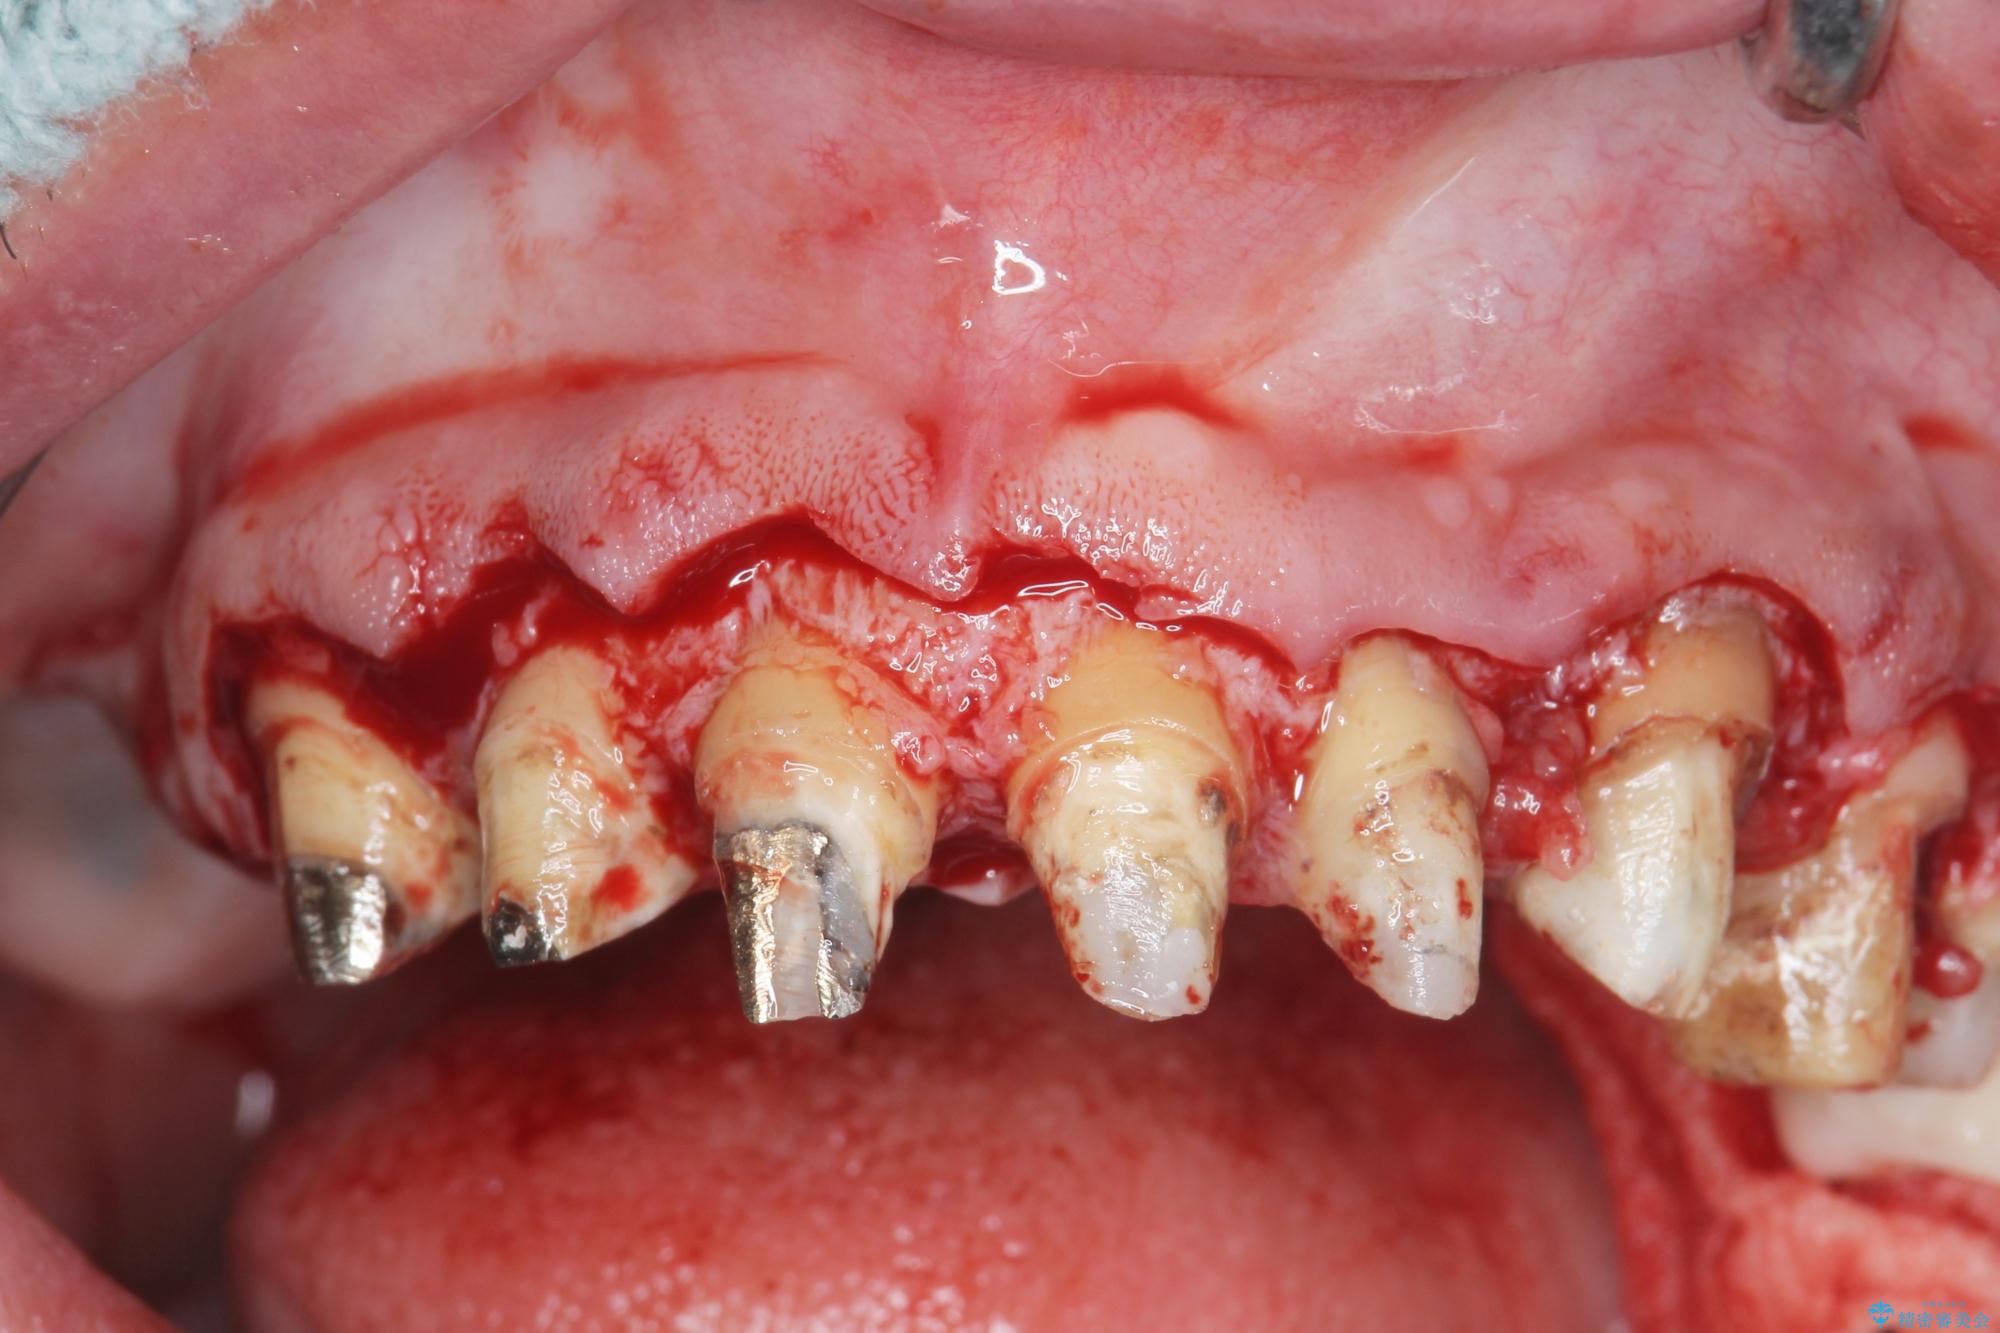

[ 歯周外科手術 ] セラミック治療後の歯ぐきの違和感

歯周組織検査を行うと歯ぐきからは容易に出血し、X線検査より歯とセラミッククラウンの適合が悪い(ピッタリと合っていない)状態が示唆され、歯ぐきの炎症を惹起している状態でした。

セラミッククラウンを除去し仮歯を装着し、歯周外科手術を行い歯ぐきの状態を改善したのち、適合の良いセラミッククラウンを再作製をする治療計画としました。